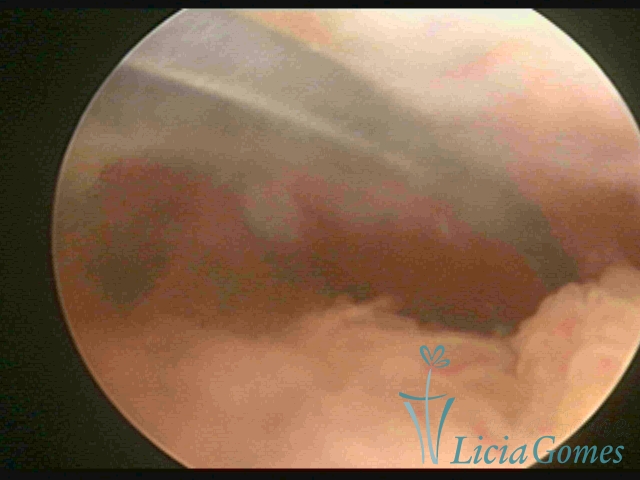

Myometrium punctured IUD